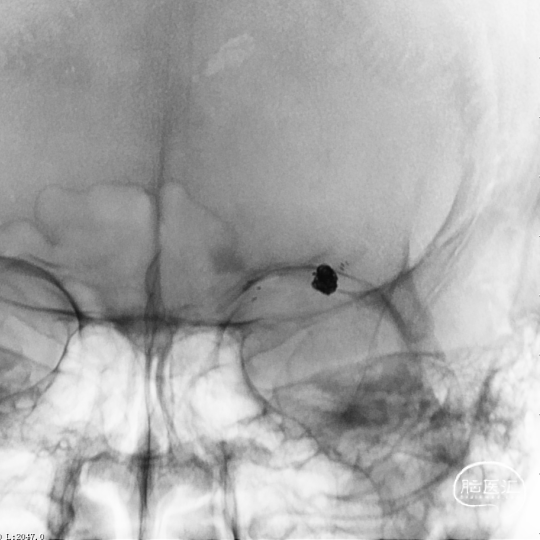

术前造影

患者推入放射科导管室平躺于检查床上,常规心电、血压监护;消毒右侧腹股沟区,铺手术巾,气管插管全身麻醉后,穿刺右侧股动脉,置入导管鞘,成功后置入超滑导丝及椎动脉导管,行左侧颈内动脉3D造影术,明确动脉瘤栓塞和辅助支架置入的工作体位。

载瘤动脉细小,经测量为0.87mm,角度为反向角度,释放支架易贴壁不良,颈内动脉段血管入路较迂曲,需要支撑力及柔顺性较好的微导管,同时避免微导管拉直血管并使血管位移而影响定位。

引入8F 导引导管及6F 中间导管至左侧颈内动脉,接加压管肝素盐水(500ml盐水2000单位肝素)4路;200cm Synchro-14微导丝配合SL-10微导管超选进入左侧大脑中动脉M1段上干备用(大脑中动脉M1段上干与动脉瘤瘤颈关系密切);200cm Synchro-14 微导丝配合Echelon-10微导管超选进入瘤体内,沿微导管填入Target 3mm×10cm 3D弹簧圈一枚成篮良好;后经SL-10微导管送入Atlas 3.0mm×24mm支架直至支架中部位于瘤颈处,缓慢释放支架,释放支架时通过半释放状态在瘤颈部小心推压将支架形成“穹窿”,穹顶部分支架可疝入瘤颈处,将宽颈动脉瘤变为窄颈。造影示支架稳定、帖壁良好;继续沿微导管行动脉瘤内弹簧圈栓塞术,先后放入2mm×6cm(两枚)、2mm×4cm、2mm×4cm、1.5mm×2cm弹簧圈共6枚;

释放支架前经导引导管缓慢注入替罗非班6ml,之后持续静脉泵入,速度5ml/h。手术历时60分钟,麻醉顺利苏醒,神经系统查体:未见阳性体征。NIHSS评分:0分;Raymond分级:Ⅰ级,mRS评分:0分。术后即刻行C-arm CT头颅扫描,未见出血,动脉瘤填塞致密,支架开放良好。